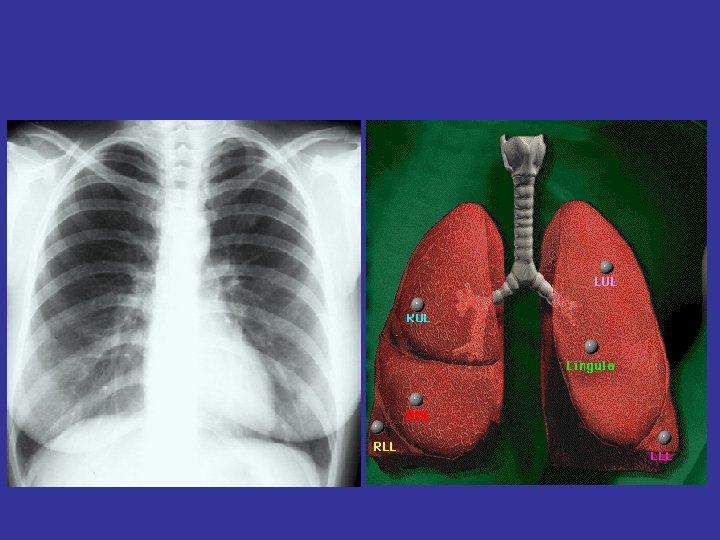

Lobes and Fissures

How to read a chest x ray ? • 1 - chest wall, bones

How to read a chest x ray ? • 1 - chest wall, bones and abdomen * bones; lesions or fractures * soft tissue ; mastectomy or soft tissue tumors • 2 - heart and mediastinum * trachea ; position & caliber * hila : lymphadenopathy * mediastinum contour : ? mass * heart : cardiac configuration • 3 - lungs opacity or lucency